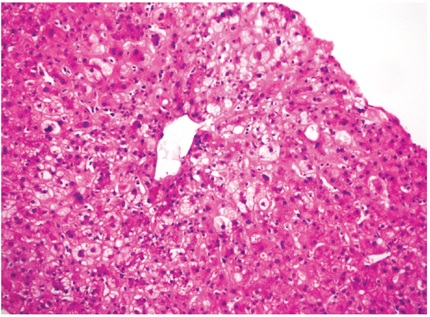

Histológicamente, se caracteriza por edema celular o balonización, necrosis aislada con formación de cuerpos acidofílicos o necrosis masiva acompañada de agregados de neutrófilos y colestasis hepatocanalicular de localización perivenular (zona 3), dada la mayor susceptibilidad de esta región a los eventos isquémicos, los cambios se hacen evidentes en las primeras 48 horas después del trasplante (Figuras 1 y 2). Cuando se toman biopsias en tiempo cero (0), o posreperfusión, son más prominentes los agregados de células inflamatorias polimorfonucleares neutrófilos. En casos severos, disminuye la inflamación y aumenta la necrosis, lo que compromete todo el ácino (panacinar) (13).

Menos frecuentemente pueden observarse necrosis en región periportal o infartos subcapsulares. Cuando hay donante con hígado graso, la lesión de reperfusión favorece la ruptura de hepatocitos, lo que libera glóbulos de grasa, que se quedan atrapados en los cordones de hepatocitos y causan obstrucción, semejando sinusoides dilatados o lipopeliosis, los cuales pueden migrar al pulmón causando embolia grasa. El pronóstico de esta condición depende directamente del porcentaje de parénquima con necrosis (14). Se incluyen en el diagnóstico diferencial el rechazo humoral, rechazo celular y complicaciones quirúrgicas, en especial de anastomosis vascular o de la vía biliar. La colestasis de presentación muy temprana también puede deberse a injertos pequeños para el donante (small-for-size), casos en los que el edema celular es muy prominente y de localización no solo perivenular sino que puede ser difusa o panacinar.